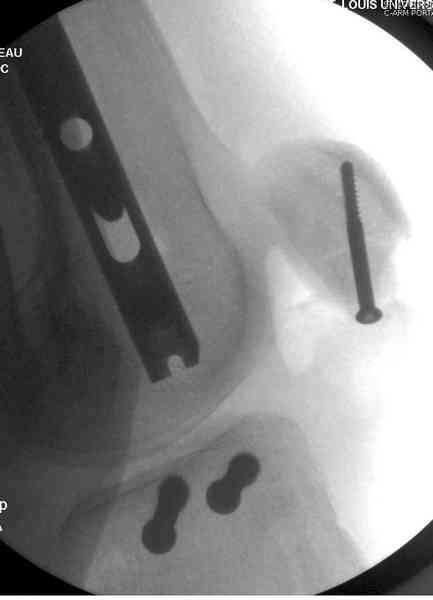

Предыдущей сменой до 4:00 утра по поводу открытого перелома бедра, тибиал плато, пилон и надколенника сделана операция.

Пострадавшему 21 г., травма скоростная, после I&D с расширением раны, на бедре сделана операция ретроградным интрамедуллярным штифтом, остеосинтез с частичной резекцией надколенника и ушивание собственной связки.

На голень наружный фиксатор, рану на бедре ушили (рана была изнутри кнаружи всего 2 см). По протоколу травматических больных, до операции обследован ангиографически, (у больного дистально не смогли определить пульсацию) сосудистый хирург подтвердил проходимость на всем протяжении магистрального сосуда нижней конечности по снимкам ангиограмм.

КТ пилона имеем.